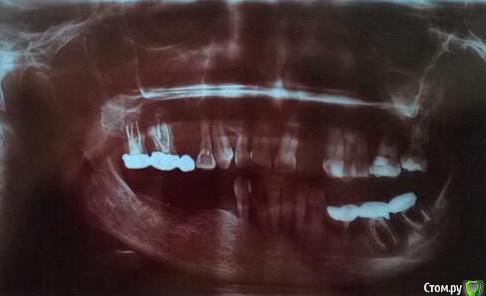

Ситуация запущена годами: зубов почти не осталось (см. снимок).

Снимок очень темный, попробуйте или перефотографировать или попросить цифровую версию. На этом ничего толком не видно.

В любом случае, не стоит начинать с эстетики, как бы вам не хотелось. если не привести в порядок боковые зубы то никакая красота на передних долго держаться не будет.